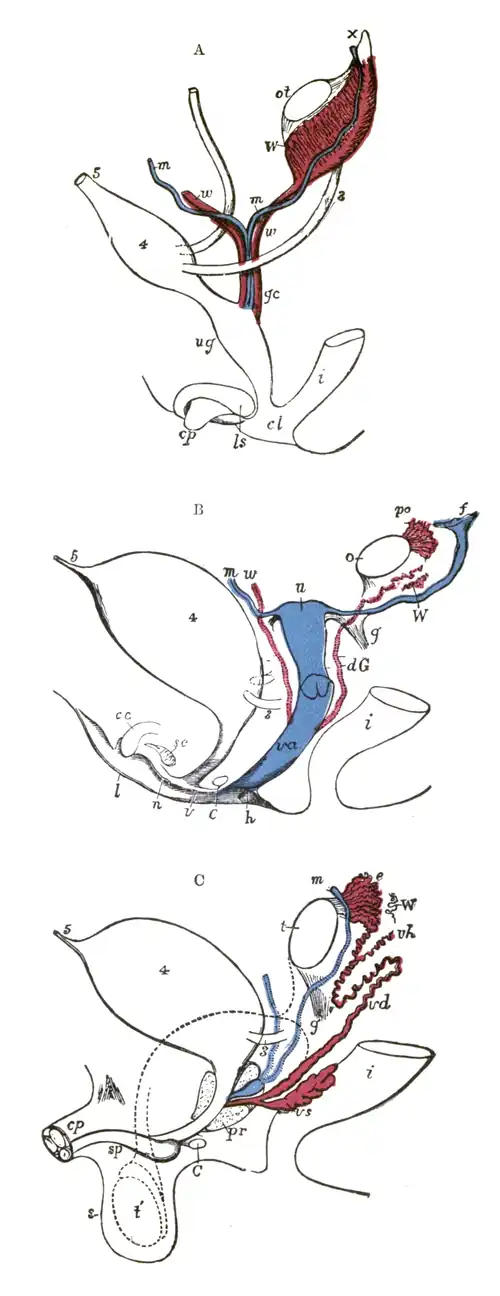

En anatomía, las trompas uterinas,[1] también conocidas como tubas uterinas, trompas de Falopio,[2] salpinges uterinas u oviductos, son dos conductos musculares separados, que conectan los ovarios y el útero o matriz de los mamíferos.

Embriología

Las trompas de Falopio derivan del extremo craneal de los conductos paramesonéfricos o conductos de Müller.

En la mujer las trompas se originan en los espacios pelvi-viscerales para terminar en la celda genital, lugar donde se sitúa el útero.[5]

Anatomía

Existen dos oviductos, cada uno conecta un ovario con el sector superior y lateral del útero.

En la mujer tienen una longitud promedio de 10 cm, con límites entre 7-14 cm.[6]

El diámetro interior es de 1 milímetro (mm) en los oviductos intramurales y de 4 mm en los pabellones de la trompa.

Se extienden a lo largo del margen superior de los ligamentos anchos del útero, desde su extremo medial o "cuernos del útero" hasta su extremo lateral en la superficie del ovario.

Cada trompa se ancla en su cara inferior, mediante una doble hoja de peritoneo llamada mesosálpinx y se abre a la cavidad peritoneal.[7][8][5][3]

Sectores de la trompa

Se pueden distinguir cuatro segmentos en la trompa de Falopio, desde el ovario hasta el útero.[9][10]